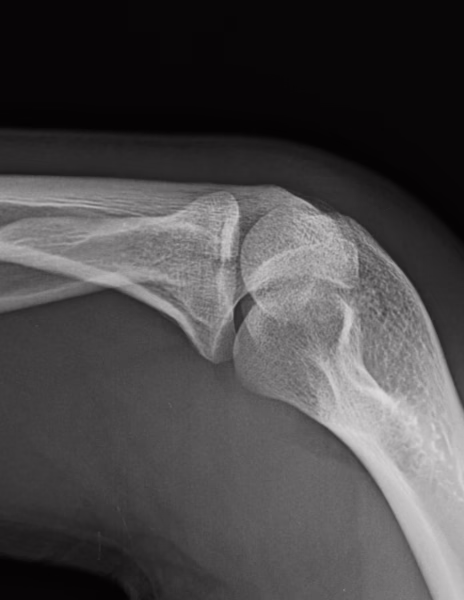

RADIOGRAFIAS AP Y LATERAL DE CODO

LAS PROYECCIONES RADIOLOGICAS OBTENIDAS NOS MUESTRA LOS SIGUIENTES HALLAZGOS:

-Tejidos blandos, a nivel de fosa de codo con aumento la densidad y grosor..

-Almohadilla grasa anterior, con el signo de la vela.

-Radio, con pérdida de la contigüidad a nivel de cabeza que involucra la porción medial, no desplazada. Resto de lo valorado de radio y cubito, sin evidencia de lesiones líticas, blásticas o perdida de la contigüidad.

-De lo valorado de humero, sin evidencia de lesiones líticas, blásticas o perdida de la contigüidad.

-Espacios articulares observados, sin evidencia alteraciones.

OPINIÓN RADIOLÓGICA:

− EN EL PRESENTE ESTUDIO RADIOGRÁFICO, EXISTE FRACTURA A NIVEL DE CABEZA DEL RADIO DE PREDOMINIO MEDIAL CON EDEMA ASOCIADO E INVOLUCRO ARTICULAR (HEMARTROSIS).

− LEER DESCRIPCIÓN Y OTORGAR VALOR DIAGNÓSTICO.

− CORRELACIONAR CON DATOS E HISTORIA CLINICA DEL PACIENTE.